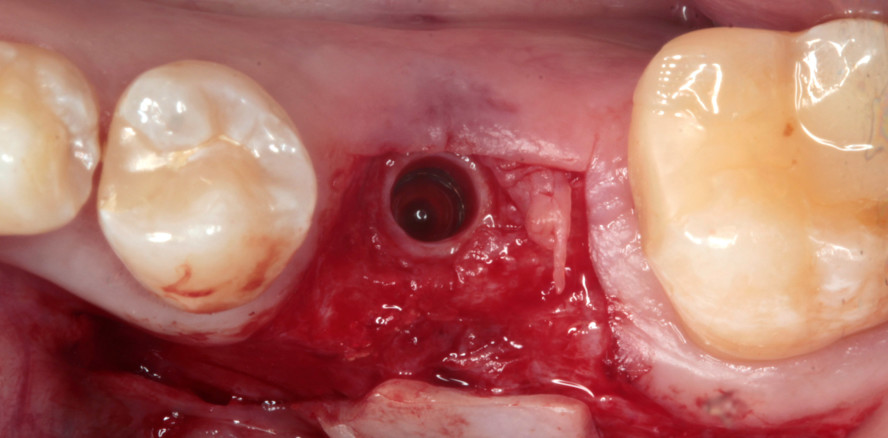

Behandlungsfall

Die Patientin suchte 2016 die Praxis nach Alio-loco-Entfernung des Zahnes 36 auf, um die Lücke implantologisch schließen zu lassen (Abb. 1). Bereits auf der präoperativen DVT-Aufnahme erkennt man das knöcherne Defizit (Abb. 2). Nach Bildung eines Mukoperiostlappens und sorgfältiger Kürretage des OP-Gebiets wird deutlich, dass zusätzlich augmentiert werden muss (Abb. 3 und 4). Trotz des spektakulär aussehenden Defizits sind solche Defekte sehr gut zu augmentieren. Es handelt sich um einen mehrwandigen Defekt, der nach mesial und distal von zwei Zähnen begrenzt ist, die das Knochenvolumen erhalten. Das Regenerationspotenzial ist also sehr hoch und begünstigt die Prognose des Erfolgs. Ein Implantat (K3Pro, Argon Dental) konnte mit hoher Primärstabilität inseriert werden (Abb. 5). Der Autor bevorzugt Knochenersatzmaterialien, die vollständig resorbieren und somit in körpereigenen Knochen umgewandelt werden können. Allogener Knochen hat genau diese gewünschten Eigenschaften. Bei dem hier verwendeten Augmentat (Osteograft, Argon Dental) handelt es sich um menschlichen Spenderknochen, der vom DIZG (Deutsches Institut für Zell- und Gewebeersatz) aufbereitet wird.